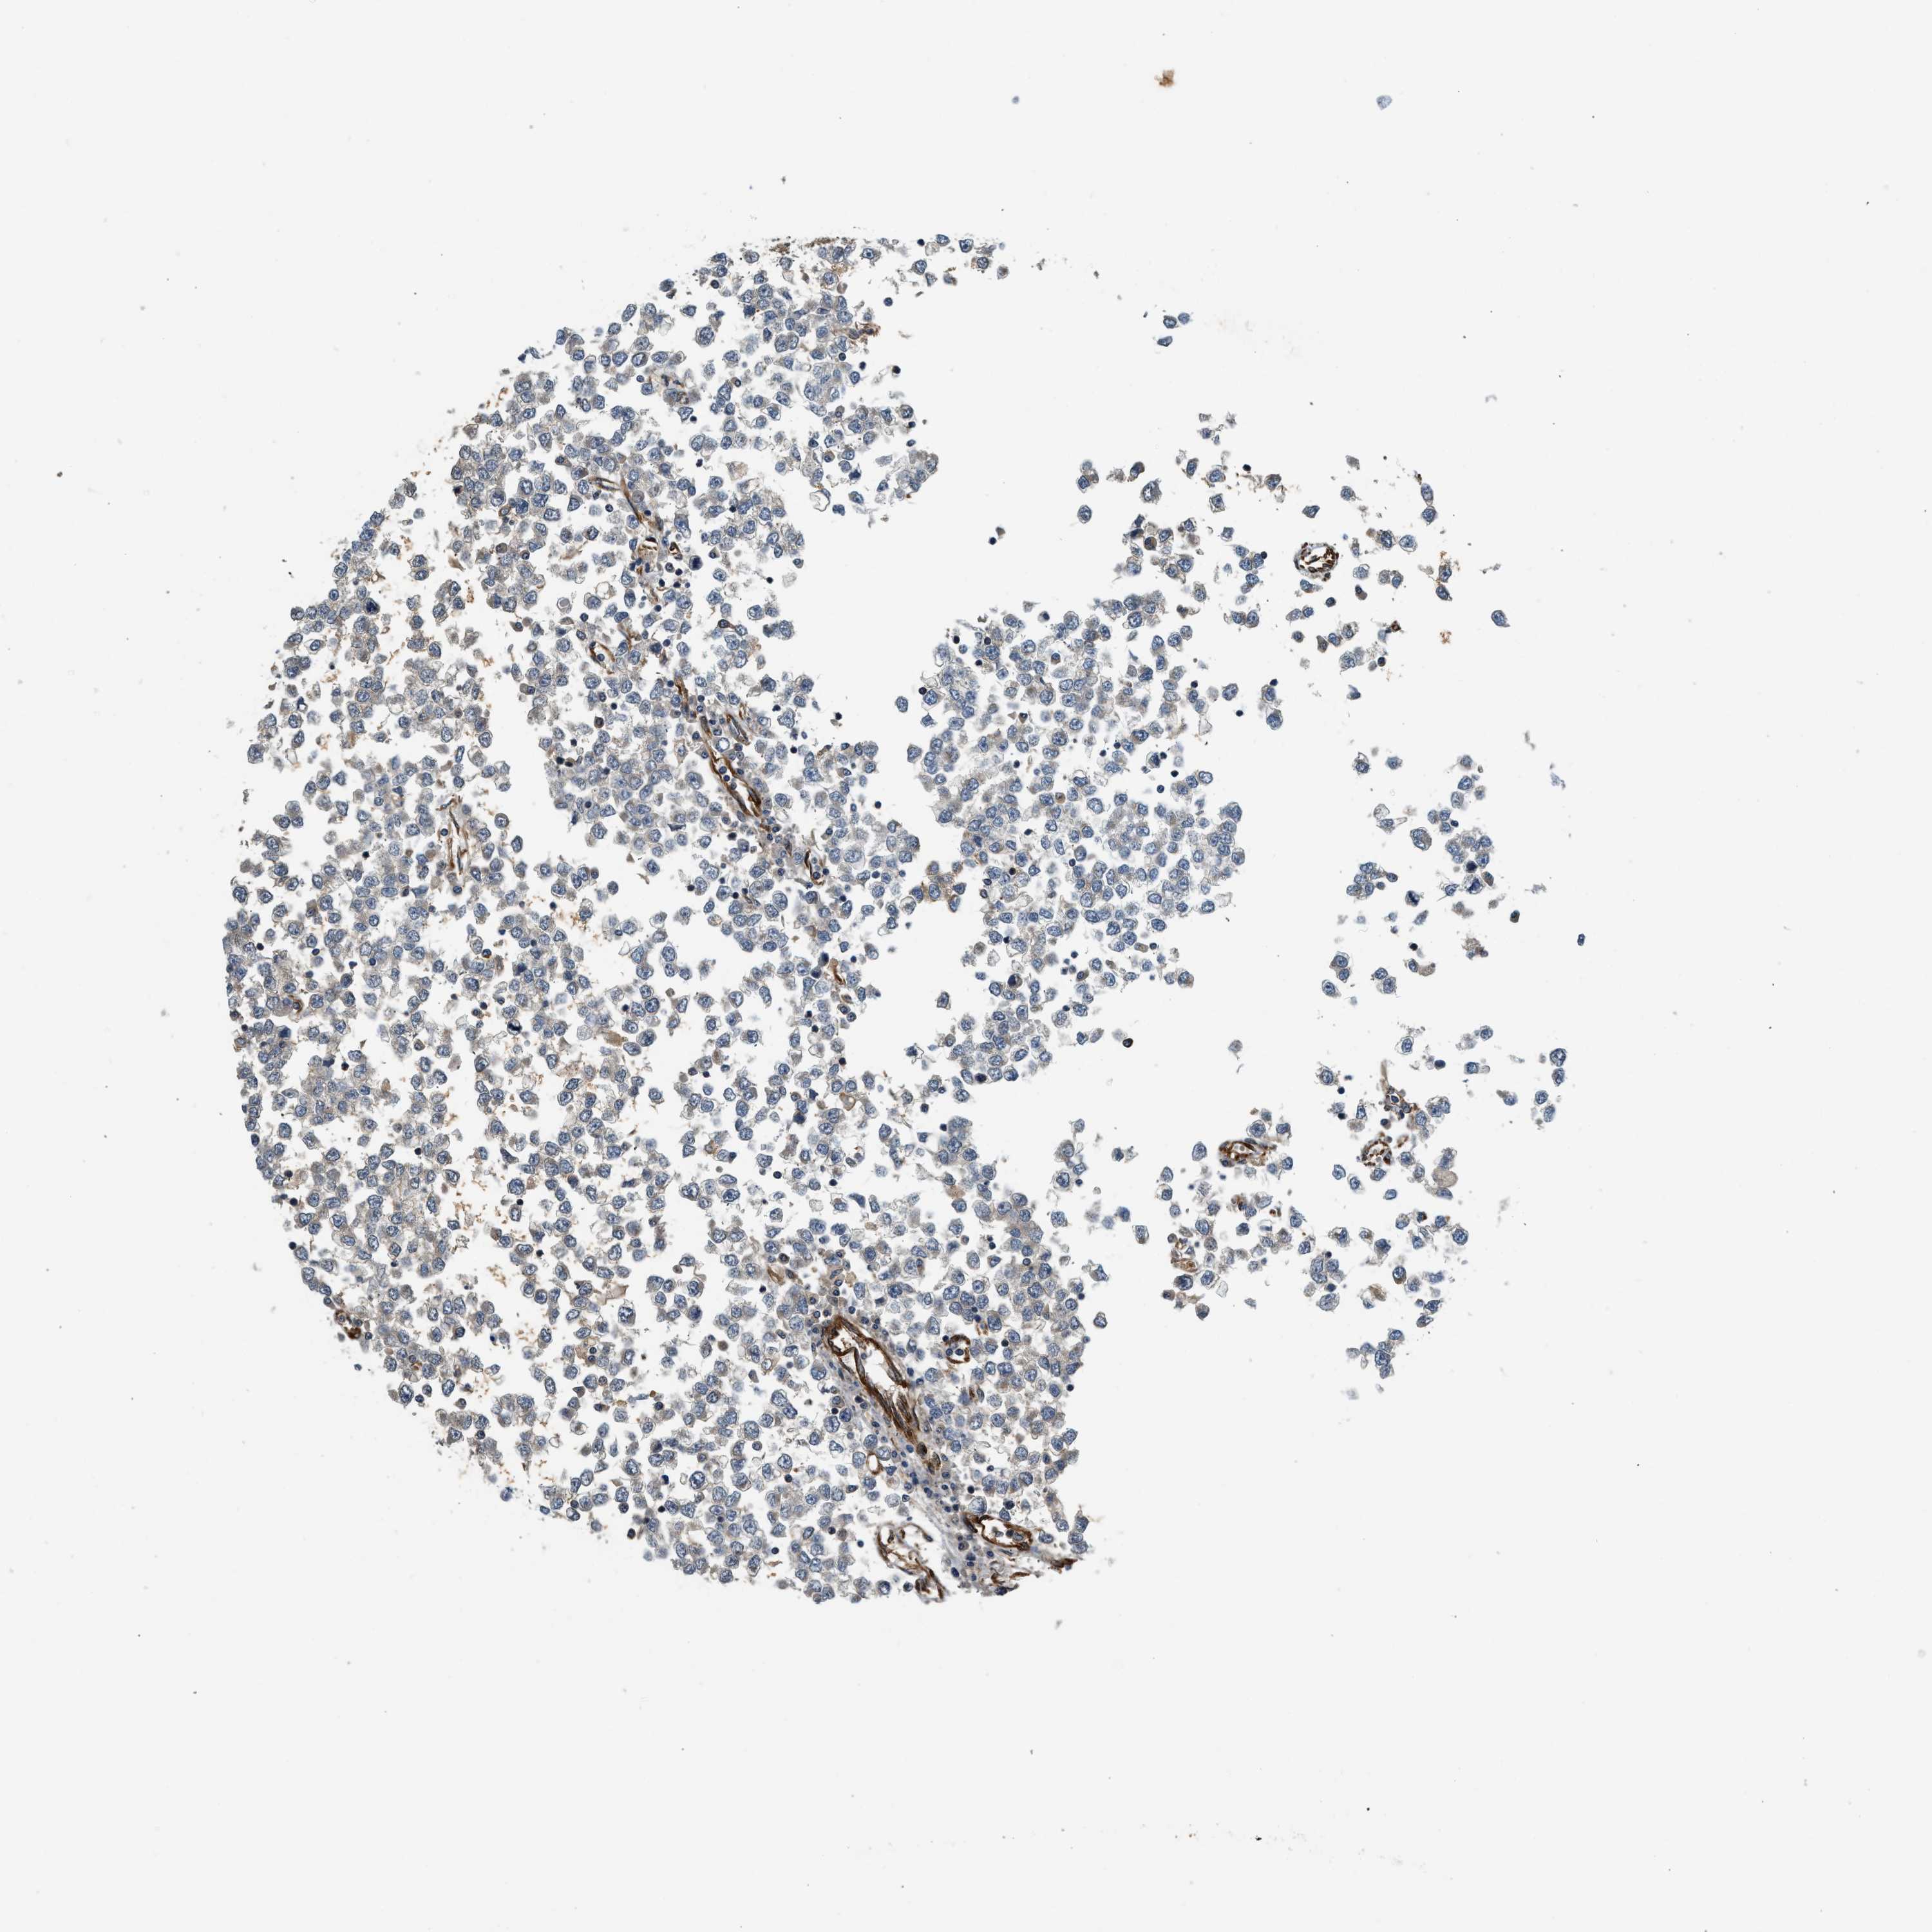

TESTIS CANCER - Protein expressioni

A mouse-over function shows sample information and annotation data. Click on an image to view it in a full screen mode. Samples can be filtered based on level of antibody staining by selecting one or several of the following categories: high, medium, low and not detected. The assay and annotation is described here.

Note that samples used for immunohistochemistry by the Human Protein Atlas do not correspond to samples in the TCGA dataset.

Antibody stainingi

Antibody staining in the annotated cell types in the current human tissue is reported as not detected, low, medium, or high, based on conventional immunohistochemistry profiling in selected tissues. This score is based on the combination of the staining intensity and fraction of stained cells.

Each image is clickable and will lead to virtual microscopy that enables deeper exploration of all samples and also displays staining intensity scores, fraction scores and subcellular localization as well as patient and tissue information for each sample.

Antibody HPA013606

Antibody HPA017964

Antibody CAB015334

Antibody CAB016402

Staining

High

Medium

Low

Not detected

Intensity

Strong

Moderate

Weak

Negative

Quantity

>75%

75%-25%

<25%

None

Location

Nuclear

Cytoplasmic/membranous

Cytoplasmic/membranous,nuclear

Carcinoma, Embryonal, NOS

Seminoma, NOS